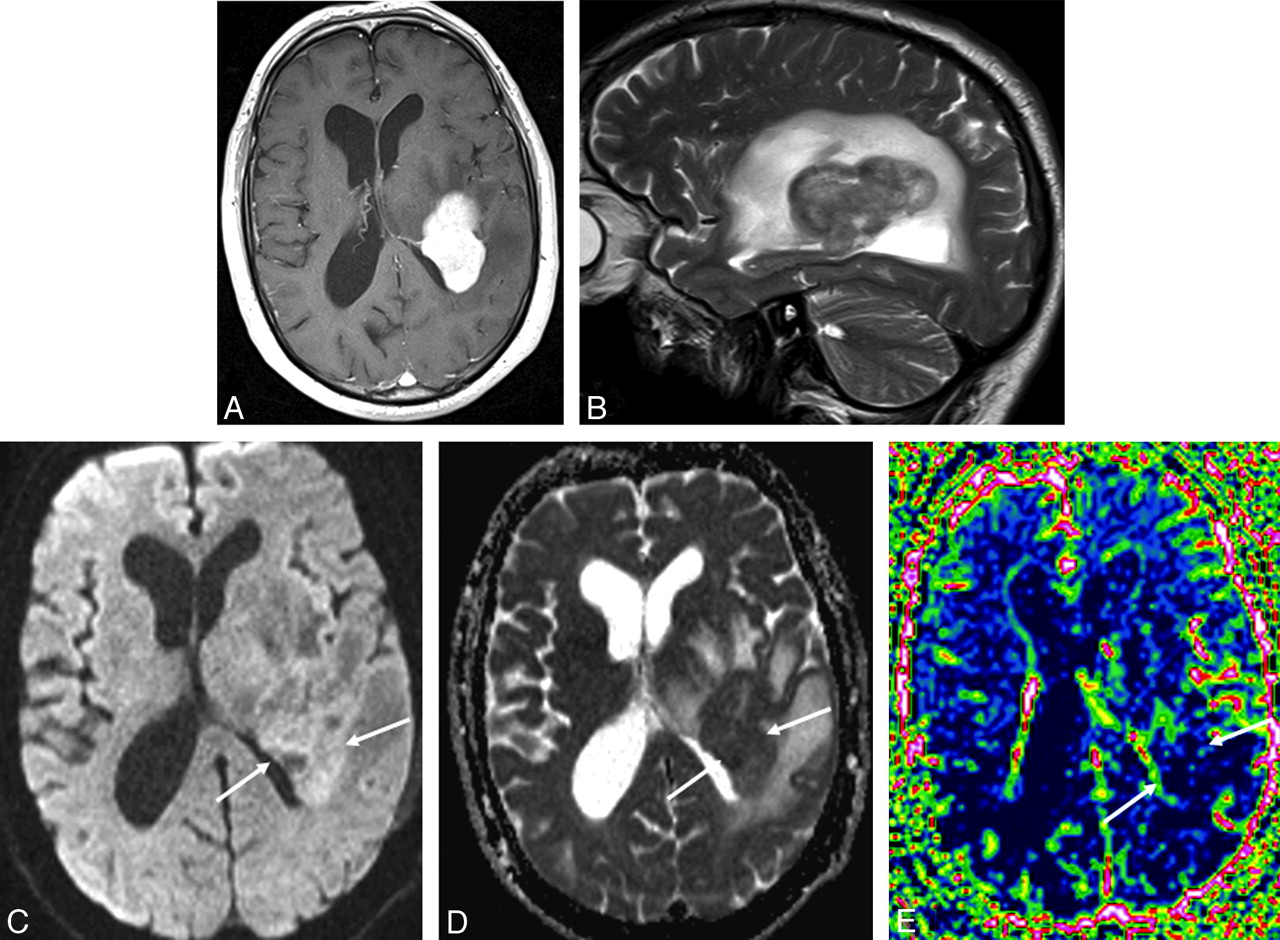

DWI measures the diffusion of water molecules in biologic tissues; diffusion within the tumor is considered a surrogate marker of tumor cellularity because intact cells constitute a barrier to water diffusion.44 Because CNS lymphomas are highly cellular tumors, water diffusion is often restricted, making them appear hyperintense on DWI and hypointense on ADC maps (Figs 4 and 6).16,40,44,45 This characteristic is shared by acute ischemic stroke, the central necrosis of brain abscesses, the solid portion of high-grade gliomas, and some metastases.45 However, PCNSL lesions often have more restricted diffusion and lower ADC values than high-grade gliomas and metastases.40,46,47

The documented importance of revascularization through angiogenesis for tumor growth has led to a growing interest in novel imaging techniques to assess tumor vascularity. Perfusion MR imaging and perfusion CT visualize nutritive delivery of arterial blood to the capillary bed in the biologic tissue (eg, tumors); postprocessing of the acquired data enables calculation of physiologic parameters, such as CBV, cerebral blood flow, mean transit time, and time to peak.49–51 PCNSLs demonstrate low CBV (Fig 6) and a characteristic intensity time curve, which is related to a massive leakage of contrast media into the interstitial space.41 Furthermore, maximum relative CBV measured in tumor tissue, calculated as a ratio to contralateral normal-appearing white matter, is typically lower in lymphomas than in other brain tumors. This characteristic finding can help to differentiate glioblastomas and metastases from lymphomas.40,52

Axial contrast-enhanced T1-weighted MR image (A), sagittal T2-weighted MR image (B), axial DWI (C), an ADC map (D), and an rCBV map (E) in a patient with PCNSL. The periventricular contrast-enhancing tumor (A) in the left parietal lobe has restricted diffusion with high signal intensity on DWI (C) with corresponding low signal intensity on the ADC map (arrows, D). Perfusion MR imaging shows low perfusion within the contrast-enhancing tumor on the rCBV map (arrows, E).